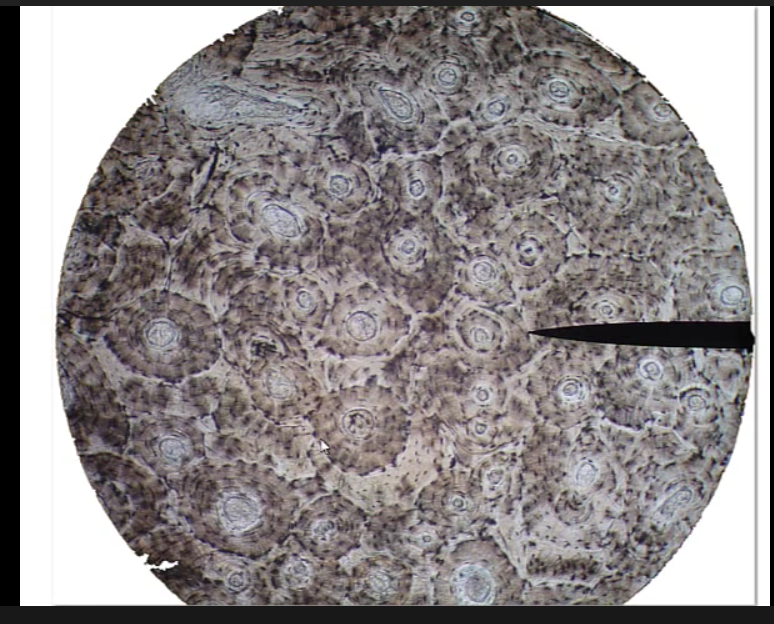

I was able to get the microscope to work, and was able to adjust between lenses and distance between lense and slide perfectly fine, and the light was also working just fine. I took these pictures myself by putting my phone to the lenses

Very healthy and vibrant looking cells, I have yet to find out what this is.

6/28/20 Edit: there seems to be a lot of epithelium and adipose, I don’t yet know what this is but it probably is the lining of a hollow organ like blood vessels or intestines. I added labels to the picture: